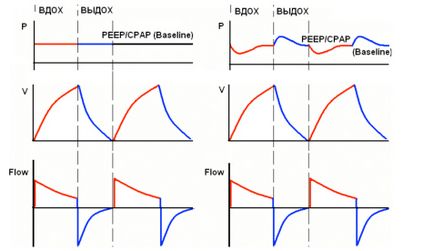

A. ábra egy ideális nyomáson gráfot CPAP.

A tényleges klinikai helyzetben, a lélegeztető nincs ideje reagálni azonnal a belégzés és kilégzés a beteg - ábra B.

Felhívjuk figyelmét, hogy az inhalálás során volt egy kis nyomáscsökkenés, és kilégzéskor - növekedést jelent.

Abban az esetben, ha az opció kiegészítve CPAP semmilyen szellőztetési mód, helyesebb nevezni Baseline nyomás, mert abban az időben a hardver belégzési nyomás (nyomás) nem állandó.

Kiindulási nyomást vagy csak alapvonal a vezérlőpulton a ventilátor általában hagyományosan jelöljük PEEP / CPAP az előre meghatározott nyomás szintje a légzőkörben, amely eszközt is megmarad az a közötti intervallum légzési ciklusok. Kiindulási fogalma nyomás, a modern koncepciók, a leginkább megfelelő azonosítja ezt az opciót szellőztető, de fontos tudni, hogy a gazdálkodás elvét PEEP, CPAP és Baseline ugyanaz. Nyomás a gráf - ez az egyik, és ugyanabban a szegmensben a «Y» tengelyen, és valójában, mondhatjuk a PEEP, CPAP és alapvonal szinonimaként. Abban az esetben, PEEP = 0, ez ZEEP (nulla kilégzési nyomás), és az alapszintű megfelel a légköri nyomás.